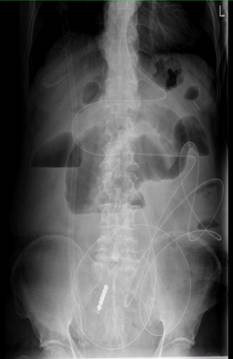

运用小肠减压管为晚期肿瘤患者实施肠梗阻球囊扩张术